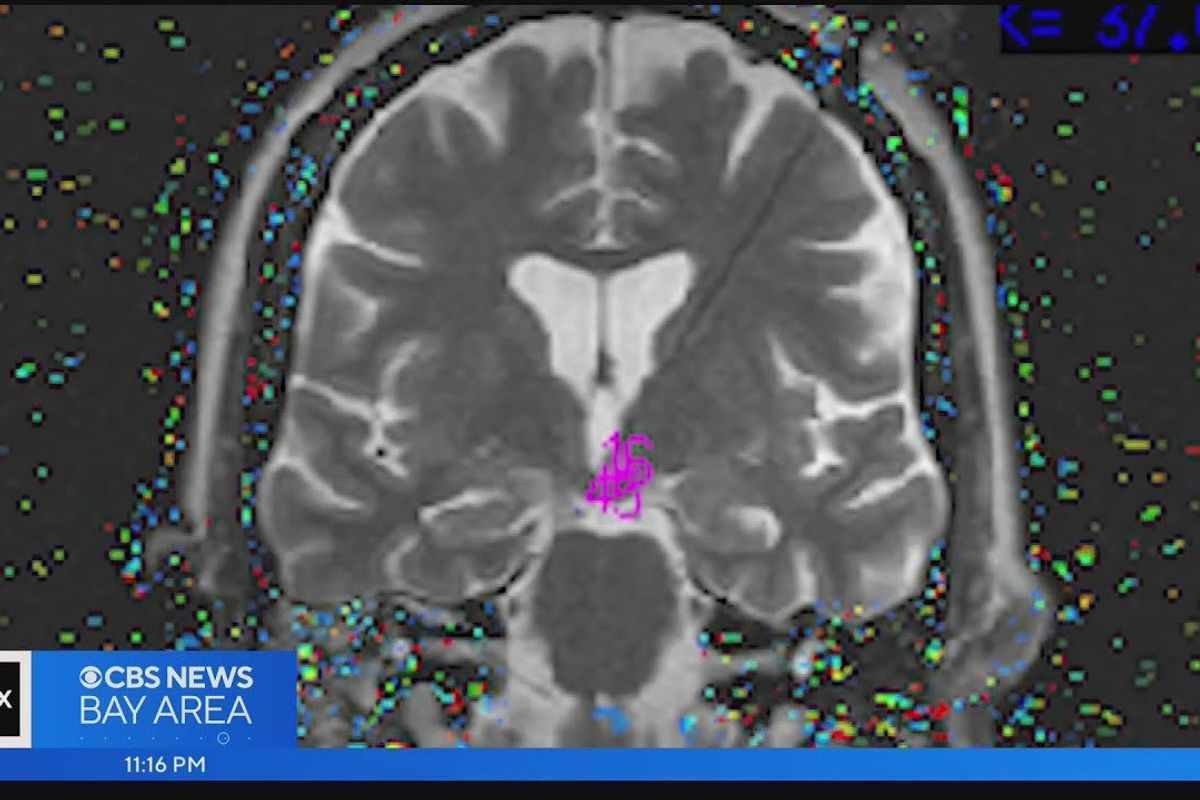

Dr. Paul Garcia, a neurologist who only worked at the hospital a few times a year, was the doctor on call. Upon hearing about Menzies' behaviors during her seizures, he was intrigued and completed an MRI of her brain. It was there that he spotted a small growth on her hypothalamus the size of a lemon seed. The doctor explained the hypothalamus controls a lot, including the nervous system.

Since the growth was deep in her brain, surgery was the only option for Menzies. After everything the woman had been through, the decision was a no-brainer...pun definitely intended. All the things that had to line up in order for Menzies to get the proper diagnosis and treatment is mind-boggling, but still, the procedure to destroy the growth was risky.